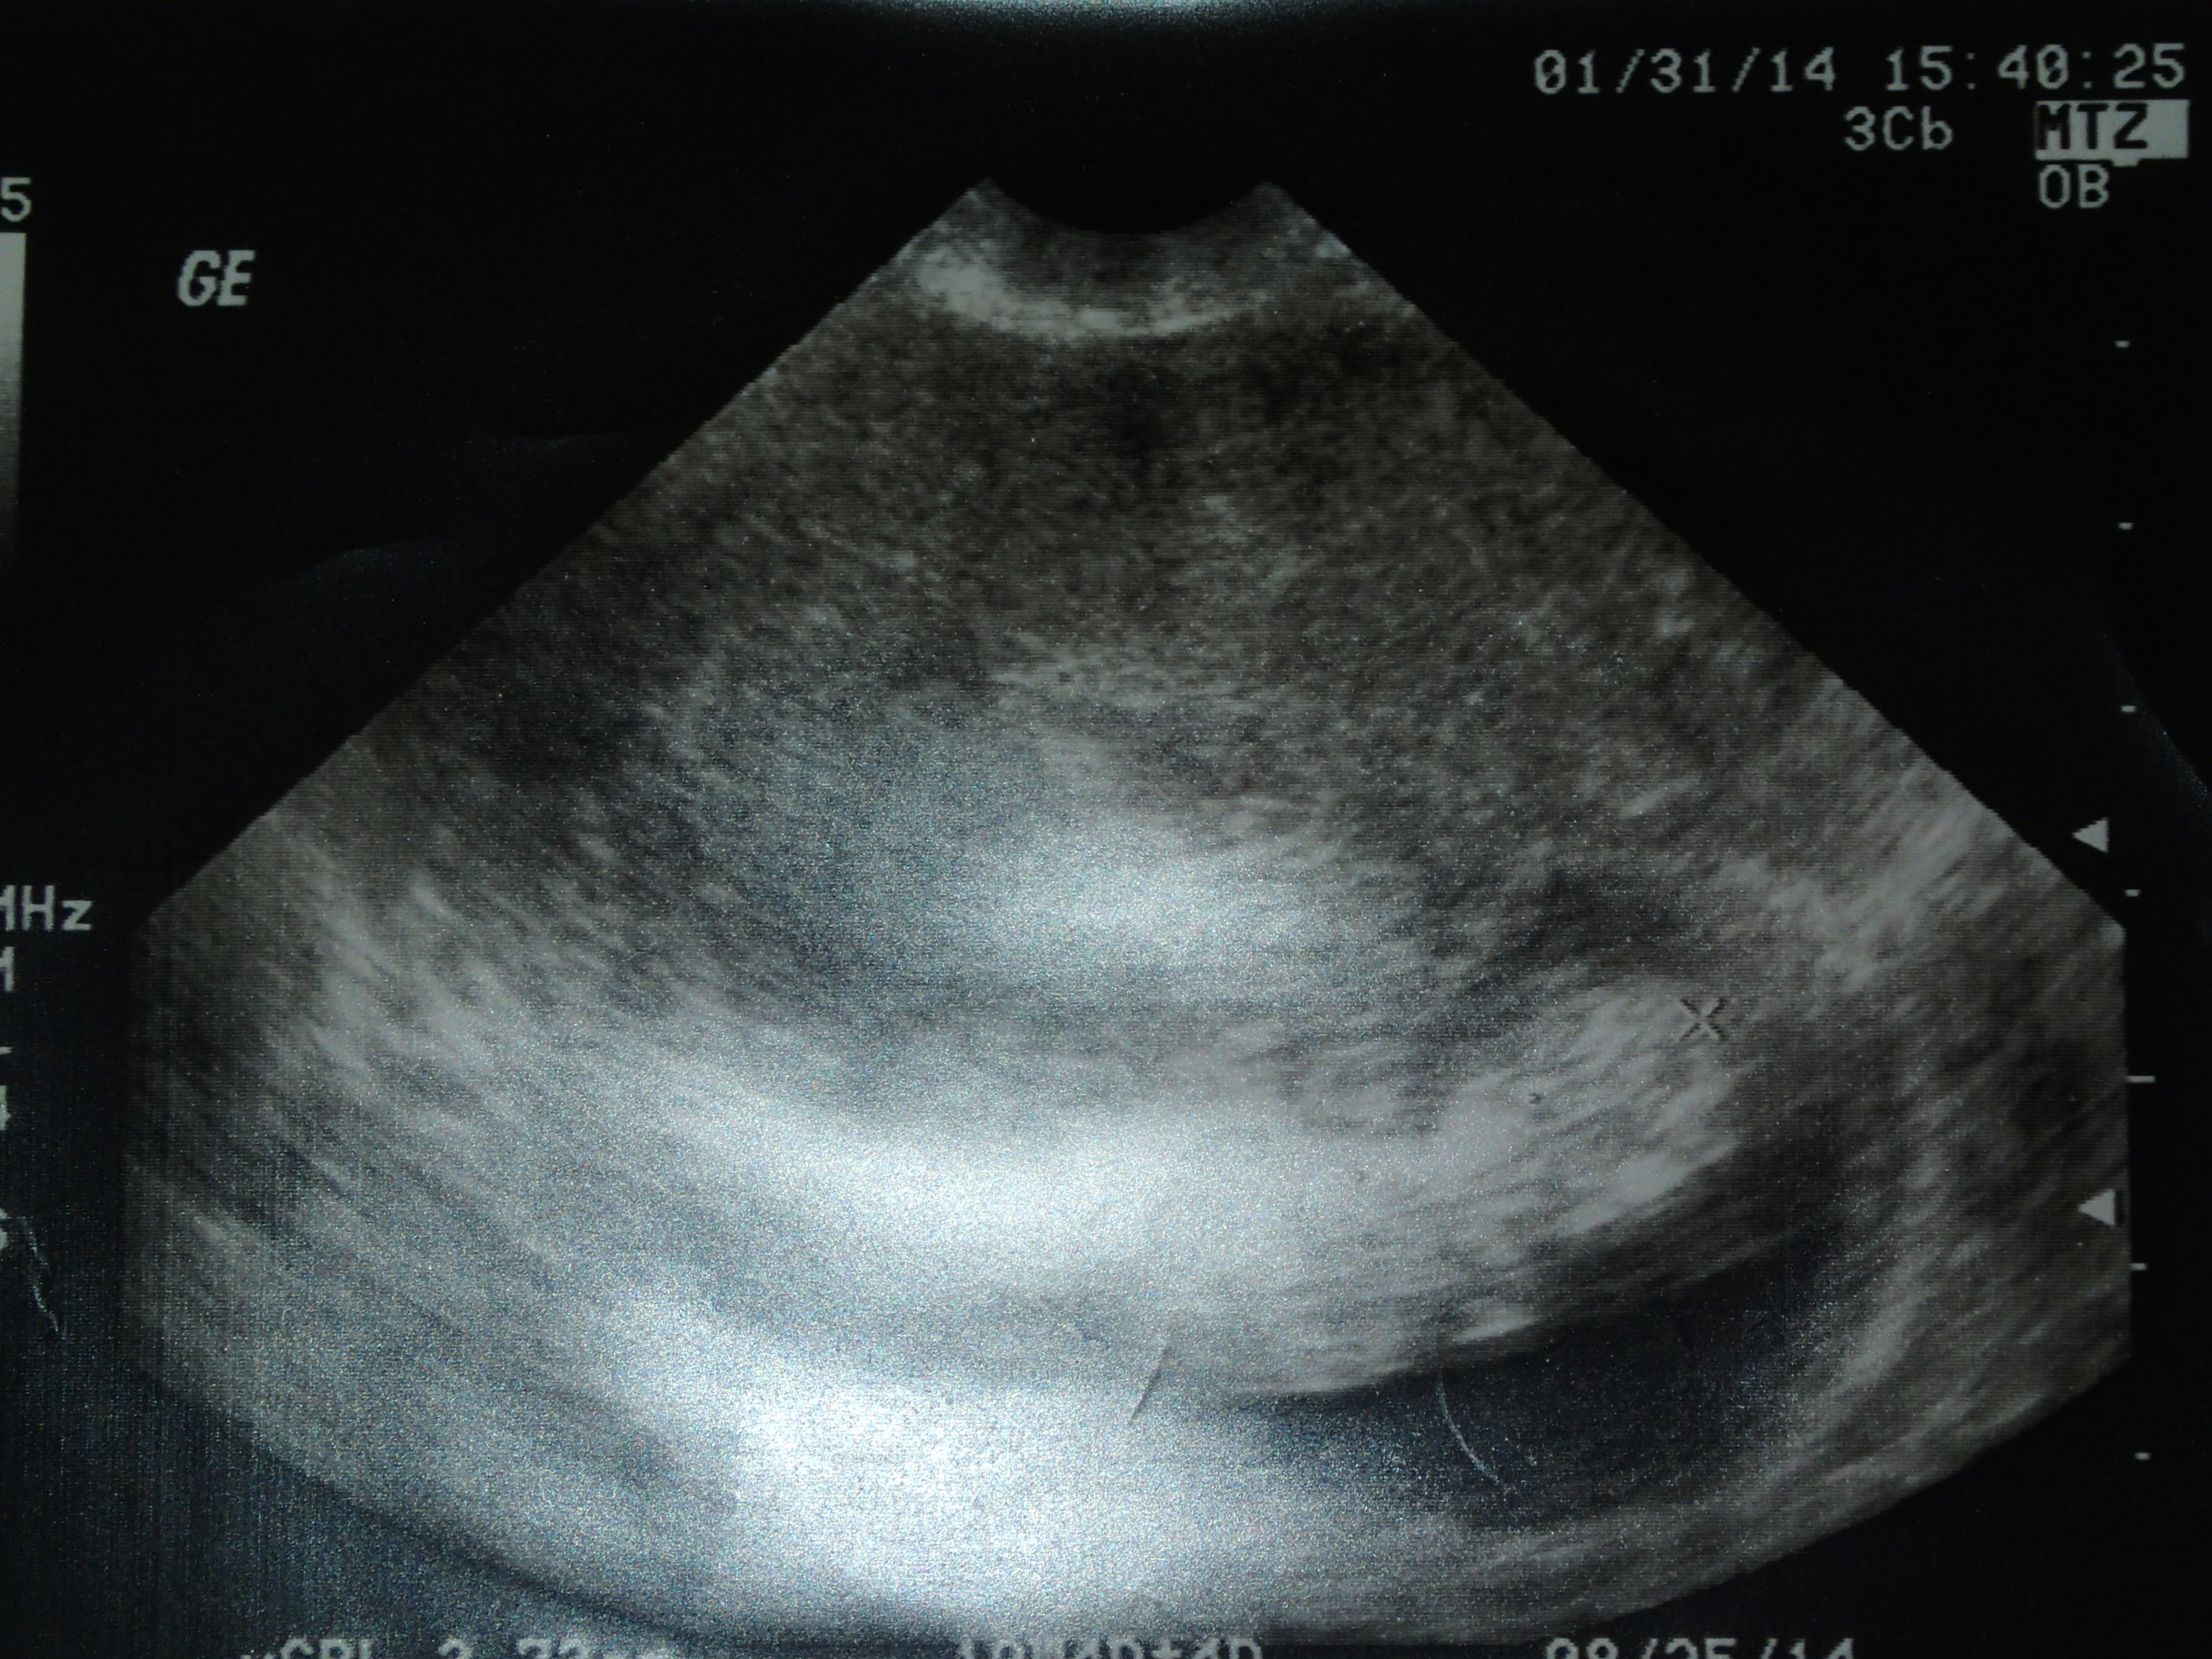

I previously mentioned February is a big month in my life. Specifically last February. A lot of it having to do with the baby girl growing inside my womb. And there was the dream. God’s words. He said to be fruitful. Multiply. Silly me thinking it had to do with my newest dream. And foolish me for not realizing the truth for an entire year. See, it has to do with something my aunt Cathy has said to me more than once. She tells me I’m blessed.

Funny thing is, there I sat last February with a group of women and opened up to them. I spoke of my struggles (shallow at best). Of knowing in my head I’m blessed, but just not feeling blessed. And there I was with a baby growing inside me. And the truth is, children are a blessing of the Lord. They are a gift. How was it that I could sit there with a baby growing inside me and not know how blessed I was? And am? How can that be?